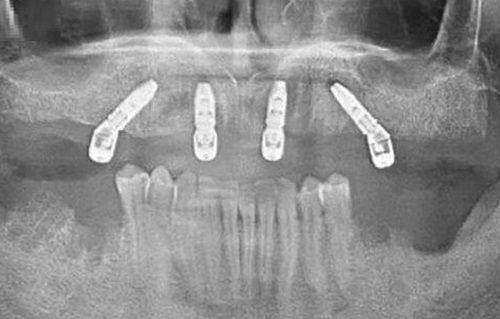

上海摩尔松江口腔医院采用精良的口腔诊疗设备,如数字化口腔全景机、口腔显微镜等,能够精细地诊断口腔问题。在治疗过程中,医院严格遵循无菌操作原则,确保患者的安心。同时,医院还注重患者的体验,提供舒适的就诊环境和贴心的服务。从预约挂号到治疗结束,每一个环节都有专人引导和服务,让患者感受到家一般的温暖。